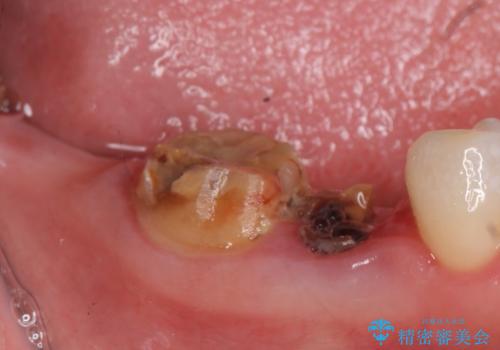

右下7は欠損しており、右下5は保存不可能だったため、インプラントによる欠損補綴を行いました。

インプラント埋入時には骨が不十分な部位に骨増生を行っております。